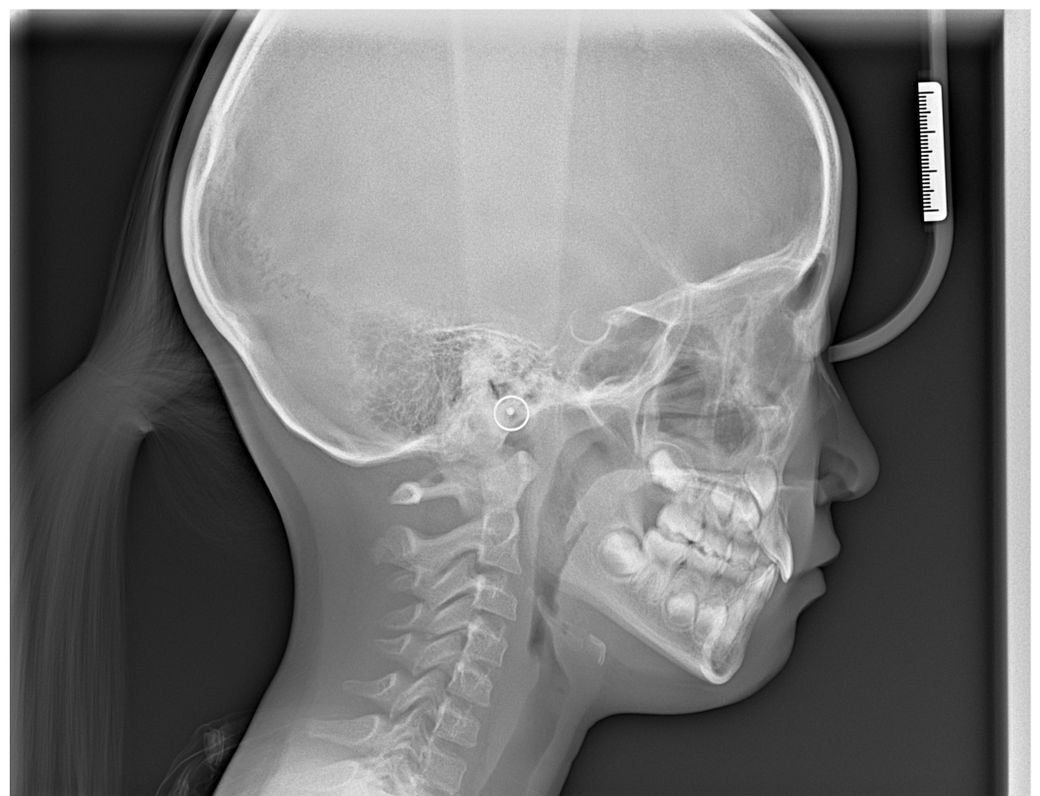

아이가 상악 앞니 측절치 2개

하악 앞니 측절치 1개 결손 입니다

영구치가 다 나면 교정을 할 예정이었는데

얼굴뼈에 비해서 상악?이 작아서

늘려야 한다고 했어요

교정 전 찍었던 파노라마도 첨부합니다